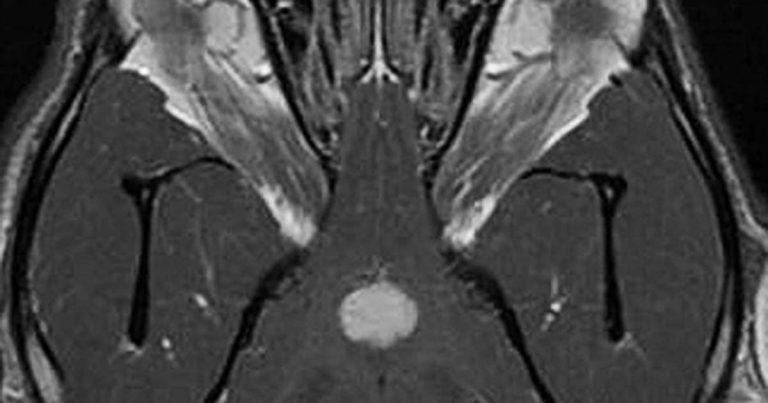

Figure 2. Dorsal 3D fast imaging employing steady-state acquisition post-contrast MRI of the brain of a dog affected by a pituitary tumour.

Diagnosis of pituitary tumours relies on advance imaging, such as CT (Figure 1) or MRI of the brain (Figure 2). Small tumours are better identified on MRI than CT. It has been estimated at least 15% to 20% of dogs with pituitary-dependent macroadenoma may develop clinical signs due to a growing pituitary tumour during the first two or three years after diagnosis, such as pacing, lethargy, aimless wandering, hiding, tight circling, head pressing and seizures.